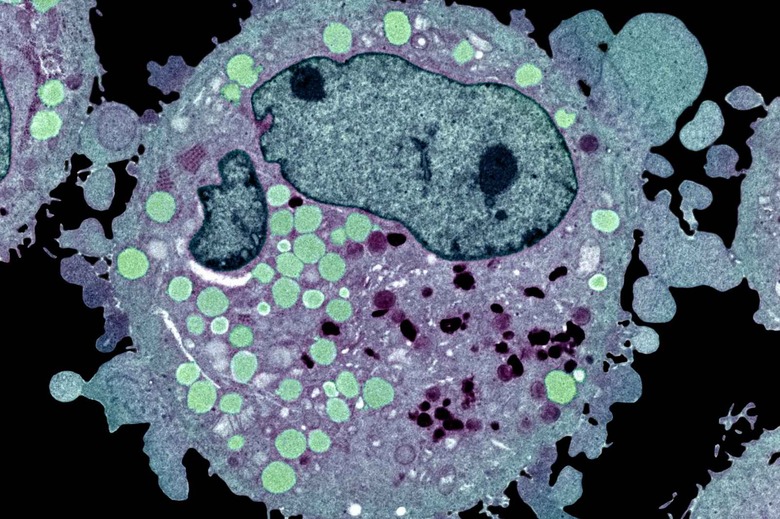

The team at 23andMe is clearly going out of its way to show that huge amounts of volunteered genetic data can boost medical research. Scientists at both 23andMe and Stanford used data from consenting customers to conduct the largest ever genetic study of basal cell carcinoma, the most typical form of skin cancer, and made numerous discoveries. They found 14 previously unidentified genetic associations with the cancer, some of which might pinpoint when you're at increased risk. Some gene regions linked to basal cell carcinoma have a larger effect on the young, hinting that environmental factors might play a greater role in getting the cancer as you age. Also, a gene marker's interactions suggest that your risk goes up when you have black or brown hair, and gene areas that maintain telomeres (chromosome ends) played their own part.